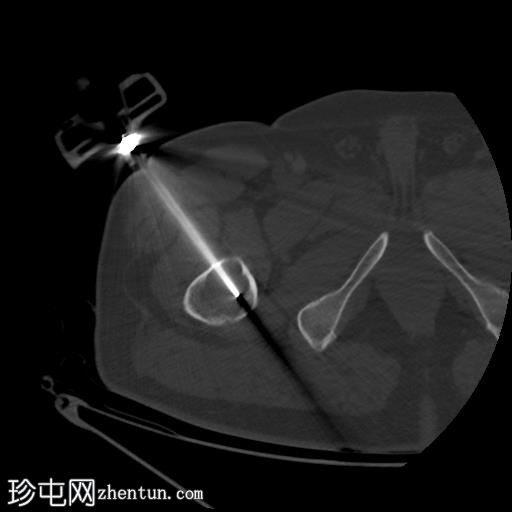

轴位骨窗

右股骨近端干骺端,股骨大转子下方可见一边界清晰的溶骨性病变。

未见皮质破坏及骨膜反应。

行CT引导下病变穿刺活检,术中及术后均未见并发症。